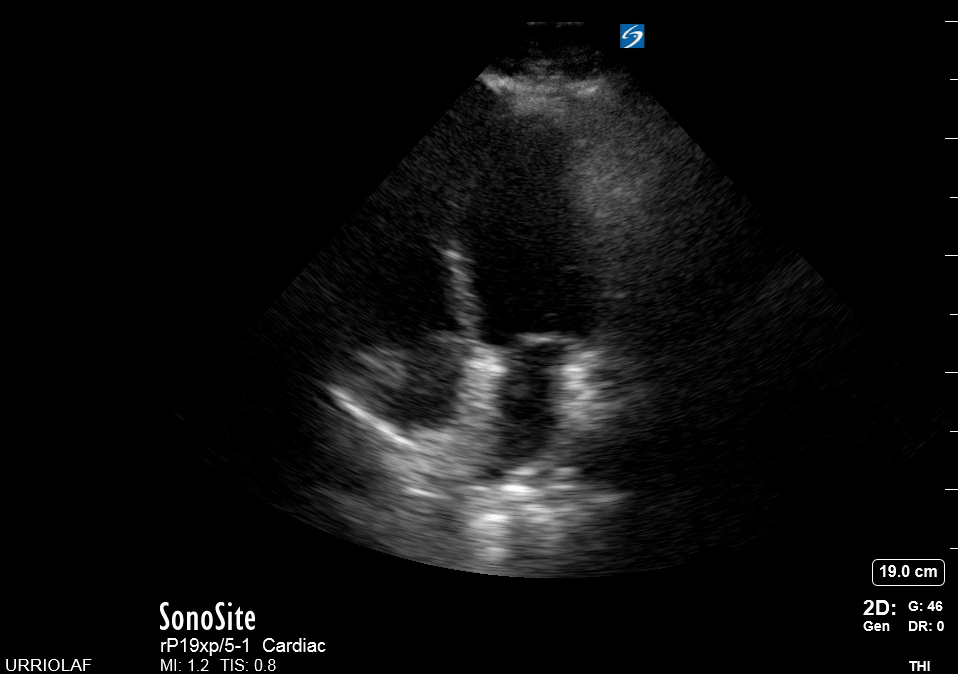

This is the standard window taught in FAST and might be the only one available during cardiopulmonary resuscitation (CPR). This view uses the liver as an acoustic window. To obtain good visualization is essential to handle the probe almost parallel to the anterior abdominal wall, trying to place it under the xiphoid process, pointing to the left shoulder. A deep inspiration or half inspiration can be useful to bring the heart closer to the probe and improve visualisation.

Remember that in the cardiac preset, the screen marking is on the right side. As a result, and unlike the FAST exam, the probe marking points towards the patient’s left. This view is used mainly to look for pericardial fluid, but it also provides information about ventricle size, chamber relationship and valvular abnormalities.